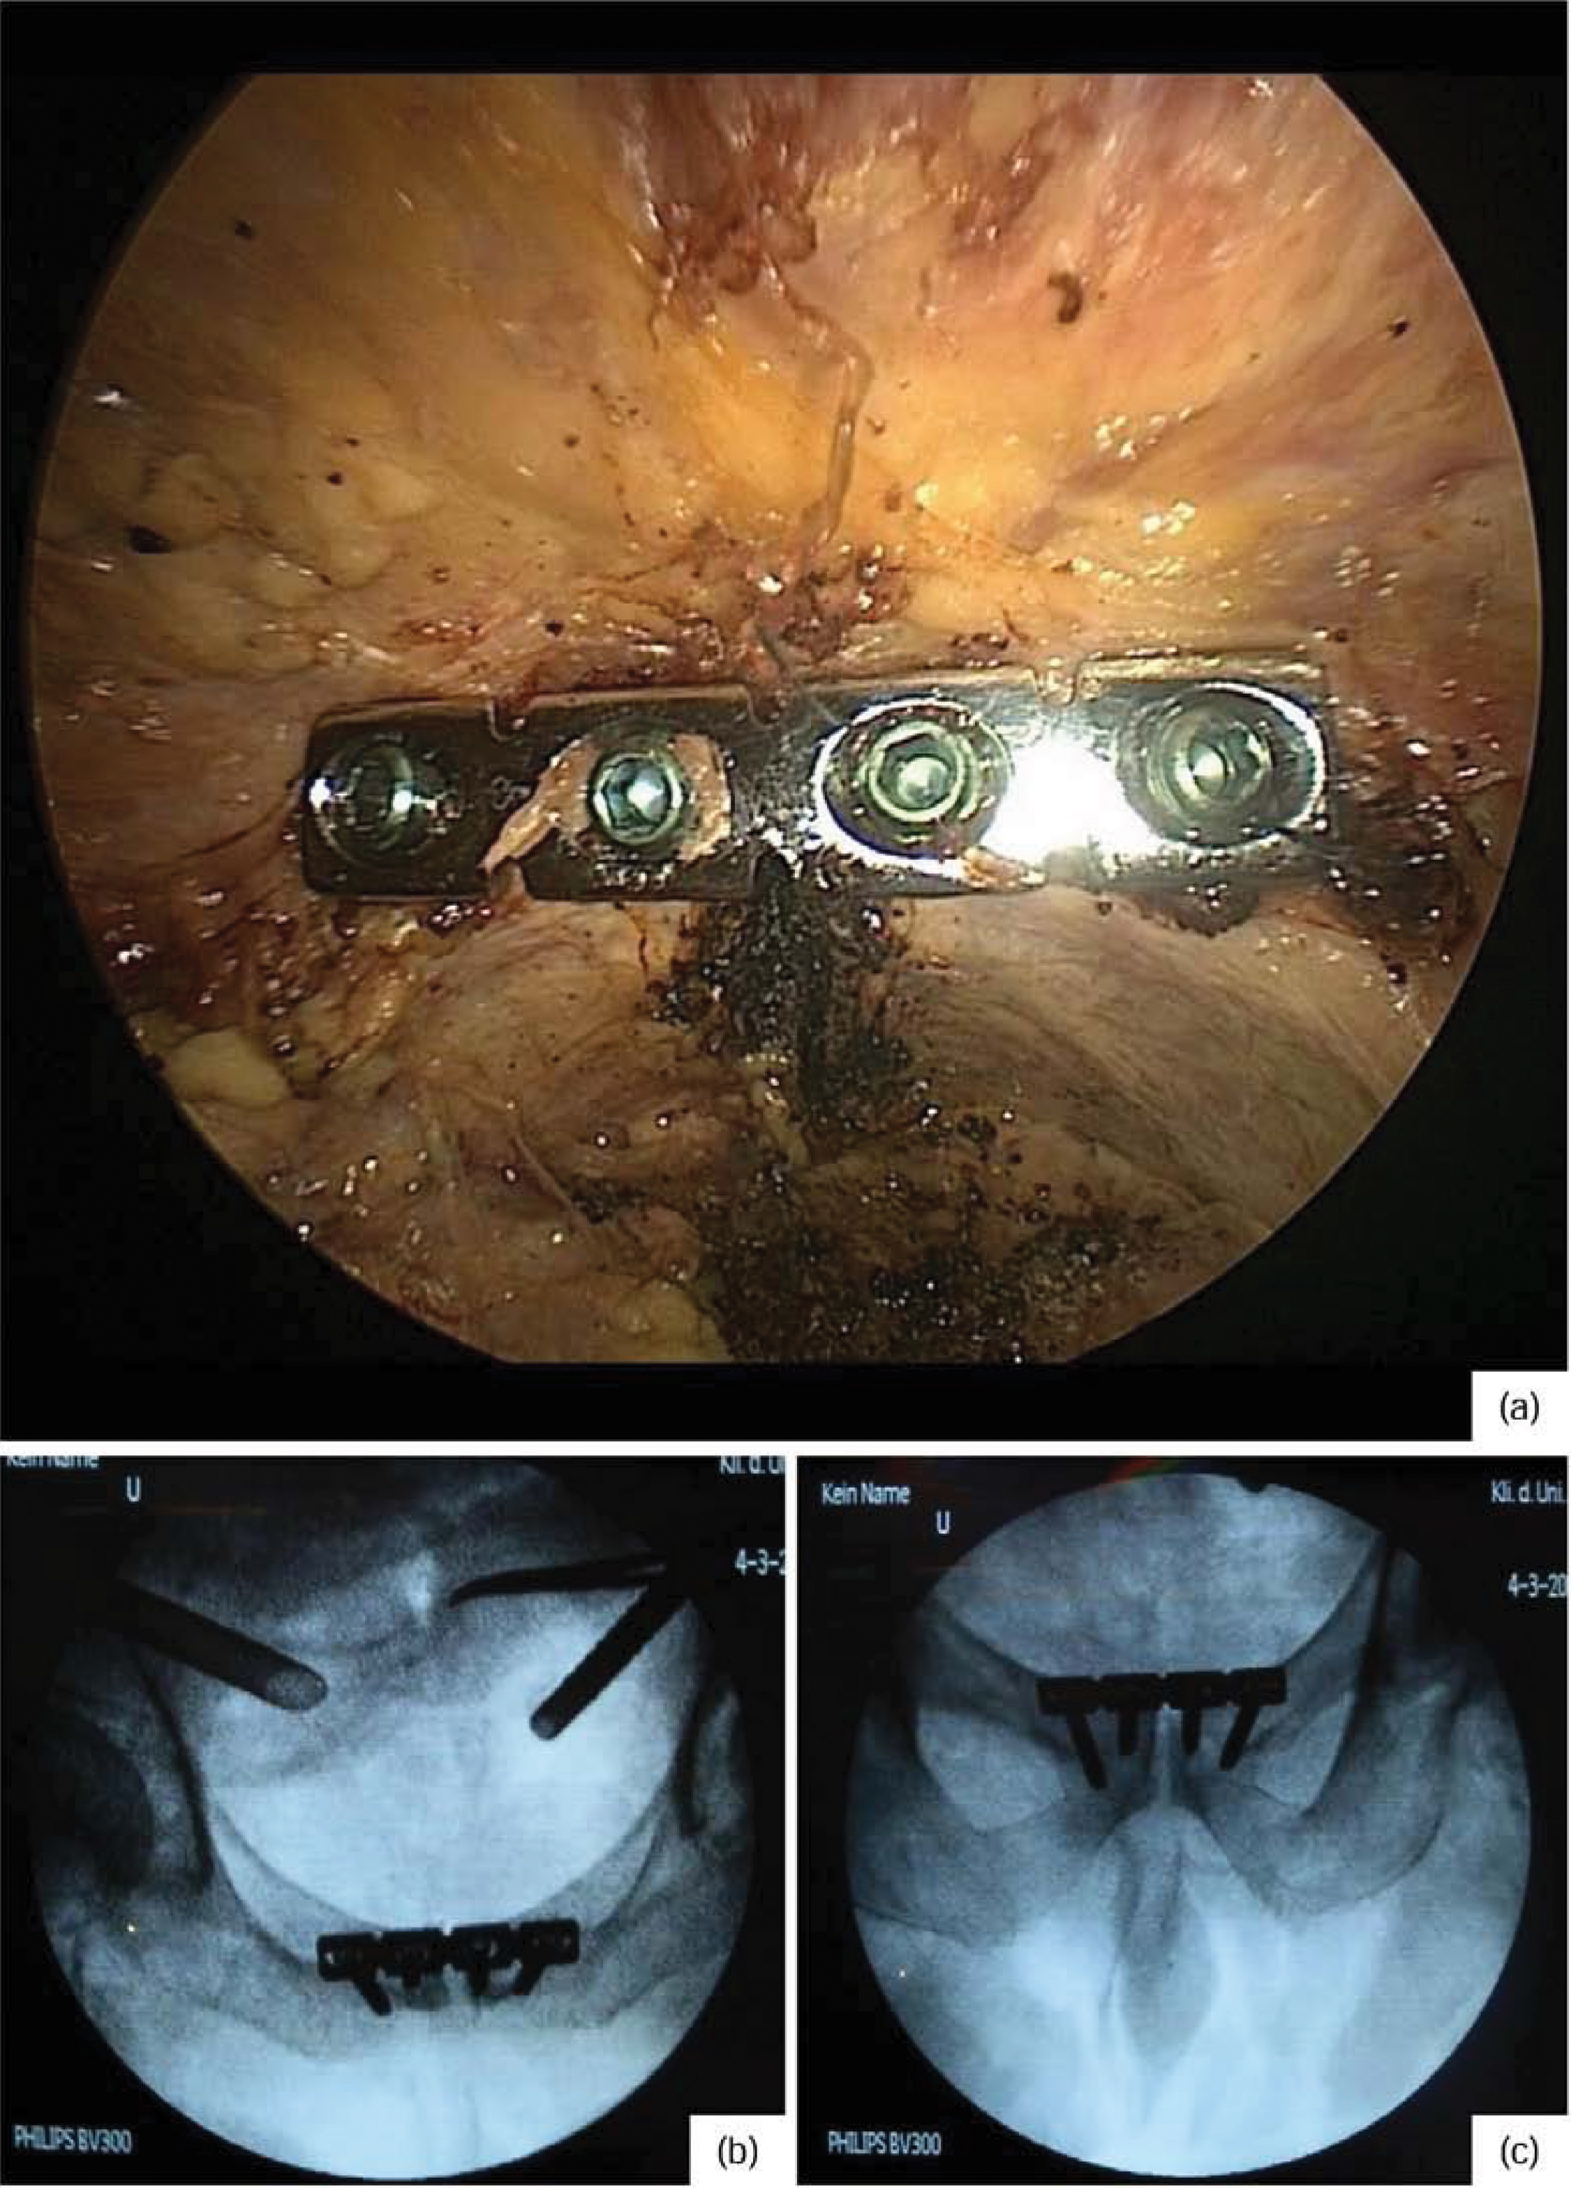

In a human cadaver, who donated himself for scientific and educational purposes, we present the minimally invasive variant of the modified Stoppa-approach step by step, both photographically and radiologically. Feasibility of the plate osteosynthesis of the symphysis is presented in a patient with open book injury via the minimally invasive approach using standard laparoscopic instruments.

Final documentation with endoscopic view of the plate (a), as well as radiological control of the plate position in 2 levels (inlet / outlet recording, b and c)